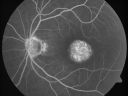

FLUORESCEIN ANGIOGRAPHY: FA shows well-circumscribed areas of hyperfluorescence in the macula of each eye.